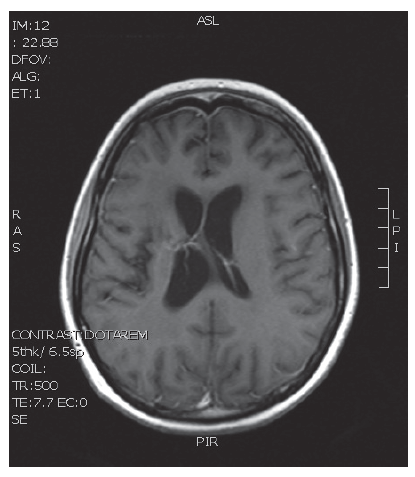

V naší kazuistice prezentujeme 25letou pacientku s negativní onkologickou rodinnou anamnézou, která dosud vážněji nestonala. Udávala asi 3 měsíce progredující bolesti hlavy a krční páteře, zvracení, postupně rozmazané vidění a parestezie horních končetin. Byla provedena magnetická rezonance, na které diagnostikován tumor mozku ve frontálním laloku vpravo, vyplňující frontální roh postranní komory velikosti 6x5 cm, midline shift, mass efekt. Dne 23. 9. 2013 ji byla na neurochirurgické klinice provedena neradikální exstirpace tumoru z parasagitální kraniotomie. Histologicky byl prokázán glioblastom multiforme gr. IV. Od 30. 10. 2013 do 12. 12. 2013 absolvovala konkomitantní radiochemoterapii (radioterapie do CLD 60,0 Gy) s temozolomidem (75 mg/m2 per os D1-42). Od ledna do dubna 2014 pokračovala v chemoterapii temozolomid solo v dávce 150 mg/m2, resp. od 2. cyklu 200 mg/m2 D1-5 ( Temodal tbl, celkem 4x). Na kontrolní MRI mozku ze dne 20. 5. 2014 byla prokázána progrese rezidua. Dne 4. 6. 2014 podstoupila druhou operaci, histologicky verifikován glioblastom multiforme s přechodem v gliosarkom. Snažili jsme se získat informace ze zahraniční literatury s léčbou gliosarkomu, bohužel se jedná o velmi vzácné onemocnění a údajů není mnoho. Nakonec byla zvolena léčba podle protokolu ICE (ifosfamid, carboplatina, etoposid), který je obdobou režimu PEI. Dávky: ifosfamid 1000 mg/m2 D1-3, carboplatina 110 mg/m2 D1 a etoposid 100 mg/m2 D1-3 v pětitýdenním cyklu. Pacientka zahájila 1. sérii od 1.7.2014 s podporou G-CSF (Neulasta s.c.). Léčbu tolerovala dobře, bez akutních či pozdních vedlejších nežádoucích účinků a významné hematologické toxicity. Po 3 cyklech podstoupila kontrolní MRI, kde popsána parciální regrese periferního sycení – rezidua tumoru. Po dalších 3 cyklech chemoterapie provedena restagingová MRI, kde popsána opět mírná regrese rezidua tumoru. Celkový stav pacientky se během léčby postupně zlepšoval, je mobilní, bez psychoorganického syndromu. Byly vysazeny kortikoidy, což vedlo k ústupu cushingoidního syndromu. Bylo rozhodnuto o pokračování v dalších 2 cyklech udržovací chemoterapie, na kontrolní MRI ze 14. 4. 2015 a 7. 7. 2015 popsána stabilizace onemocnění.